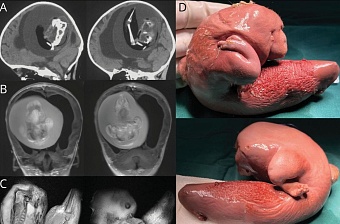

Плод близнеца обнаружили в голове годовалой девочки